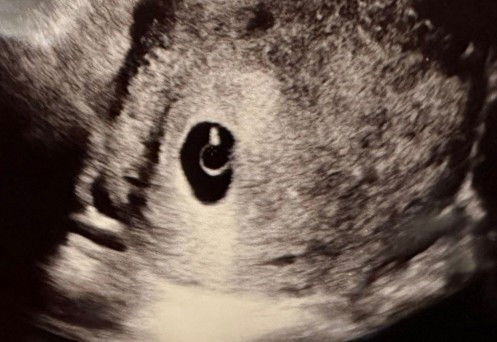

ภาพอัลตราซาว 6W คุณแม่ท่านอื่นเป็นเหมือนกันไหมคะ ปกติไหมค่ะ

ไปอัลตราซาวด์มาค่ะ รอบนี้ได้ยินเสียงหัวใจน้อง และเห็นขนาดของน้องค่ะ ของแม่ๆท่านอื่นอายุครรภ์ประมาณนี้แบบเดียวกันไหมคะ#ขอบคุณล่วงหน้านะคะ